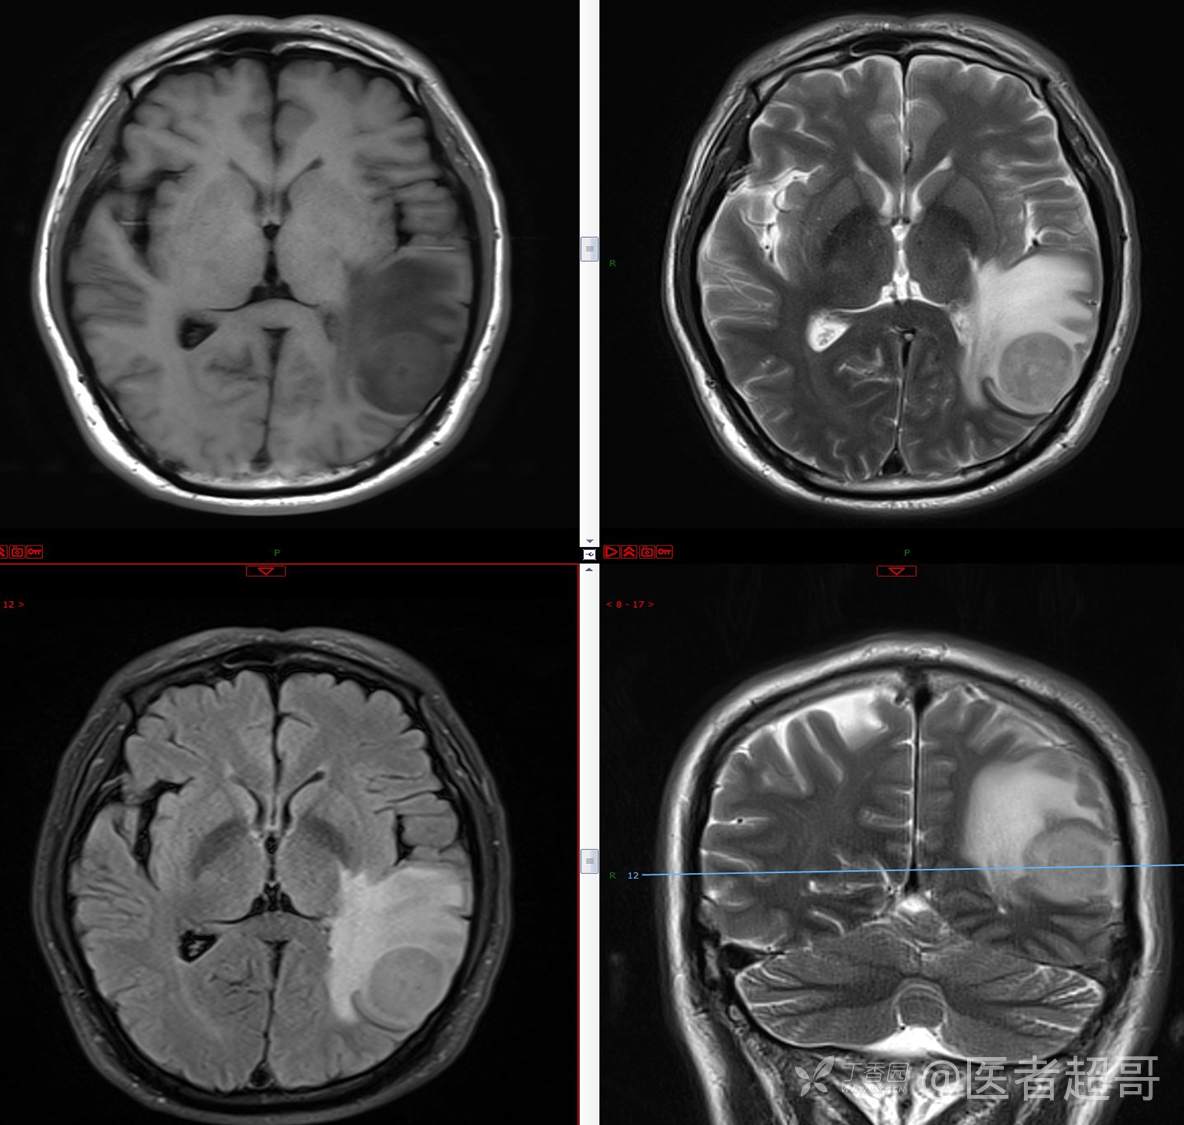

比较典型病例,CT、MRI齐全,请分析,领丁当!

男,56岁

主 诉:查体发现颅内占位10天。

现病史:患者于约10天前于我院查体时行颅脑MRI提示左侧顶叶占位病变,无头痛头晕,无恶心呕杜,无肢体活动不利,无感觉异常,现患者为求进一步治疗,就诊于我科门诊,门诊以“颅内占位性病变”收入我科。患者自发病以来,神志清,精神可,饮食及睡眠差,大小便无明显异常,体重无明显变化。